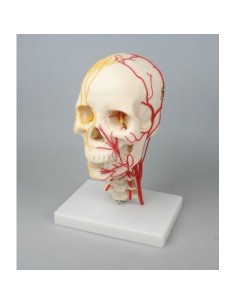

Dal cranio in 22 parti con incastri magnetici ai modelli di colonna vertebrale, da quelli di articolazioni a quelli di cuore, ogni pezzo della nostra collezione è progettato per un’immersione totale nello studio dell’anatomia umana. I nostri modelli, realizzati tramite scansioni di ossa vere, garantiscono un’esperienza tattile autentica e una fedeltà di peso quasi identica agli originali.

Essenziali per studenti e professionisti, i nostri modelli anatomici sono strumenti didattici che permettono di osservare le strutture anatomiche con precisione, eliminando la necessità di dissezioni o studi invasivi. Sono inoltre utili per spiegare ai pazienti le patologie, rendendo la comunicazione più efficace e risparmiando tempo prezioso.